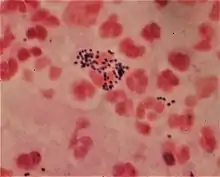

Gram stain (Gram staining or Gram's method), is a method of staining used to classify bacterial species into two large groups: gram-positive bacteria and gram-negative bacteria. It may also be used to diagnose a fungal infection.[1] The name comes from the Danish bacteriologist Hans Christian Gram, who developed the technique in 1884.[2]

Gram staining differentiates bacteria by the chemical and physical properties of their cell walls. Gram-positive cells have a thick layer of peptidoglycan in the cell wall that retains the primary stain, crystal violet. Gram-negative cells have a thinner peptidoglycan layer that allows the crystal violet to wash out on addition of ethanol. They are stained pink or red by the counterstain,[3] commonly safranin or fuchsine. Lugol's iodine solution is always added after addition of crystal violet to strengthen the bonds of the stain with the cell membrane.

Gram staining is almost always the first step in the identification of a bacterial group. While Gram staining is a valuable diagnostic tool in both clinical and research settings, not all bacteria can be definitively classified by this technique. This gives rise to gram-variable and gram-indeterminate groups.

Gram stains are performed on body fluid or biopsy when infection is suspected. Gram stains yield results much more quickly than culturing, and are especially important when infection would make an important difference in the patient's treatment and prognosis; examples are cerebrospinal fluid for meningitis and synovial fluid for septic arthritis.[9][10]

Gram-positive bacteria have a thick mesh-like cell wall made of peptidoglycan (50–90% of cell envelope), and as a result are stained purple by crystal violet, whereas gram-negative bacteria have a thinner layer (10% of cell envelope), so do not retain the purple stain and are counter-stained pink by safranin. There are four basic steps of the Gram stain:

After decolorization, the gram-positive cell remains purple and the gram-negative cell loses its purple color.[17] Counterstain, which is usually positively charged safranin or basic fuchsine, is applied last to give decolorized gram-negative bacteria a pink or red color.[3][18] Both gram-positive bacteria and gram-negative bacteria pick up the counterstain. The counterstain, however, is unseen on gram-positive bacteria because of the darker crystal violet stain.